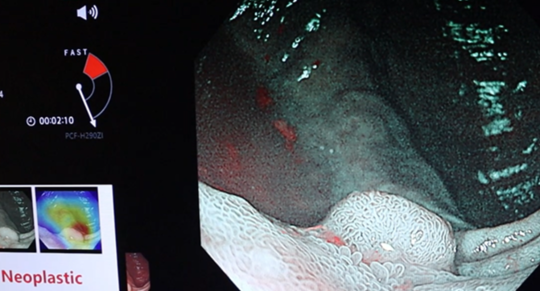

AI(人工知能)内視鏡検査支援システムによる最新の内視鏡検査

山クリニックでは経験豊富な内視鏡専門医とAI検査支援システム併用の検査を胃カメラでも大腸カメラでも両方の検査で受けることができます

大腸カメラ(下部消化管内視鏡検査)

AIと専門医の目で瞬時にポリープを発見

NBI画像をAIと専門医の目で診断

AI内視鏡検査支援プログラム導入のお知らせ

AI内視鏡検査支援プログラムCADEYE(FUJIFILM)を2025年4月より導入しました。国立がん研究センター内視鏡部での経験豊富な5名の専門医で検査を行っておりますが、さらにAI検査支援も加えてより質の高い内視鏡検査を行います。AI内視鏡をご希望の方はお気軽にお問い合わせください。

AI内視鏡診断システム導入のお知らせ

AI内視鏡診断支援システムEndoBRAIN(ワンモニター型)を2024年11月より導入しました。北関東エリア(群馬/埼玉/栃木/茨城/千葉)では初導入(オリンパス社調べ)となります。国立がん研究センター内視鏡部での経験豊富な専門医で検査を行っておりますが、さらにAI診断も加えてより質の高い内視鏡検査を行います。AI内視鏡をご希望の方はお気軽にお問い合わせください。詳しくはこちら